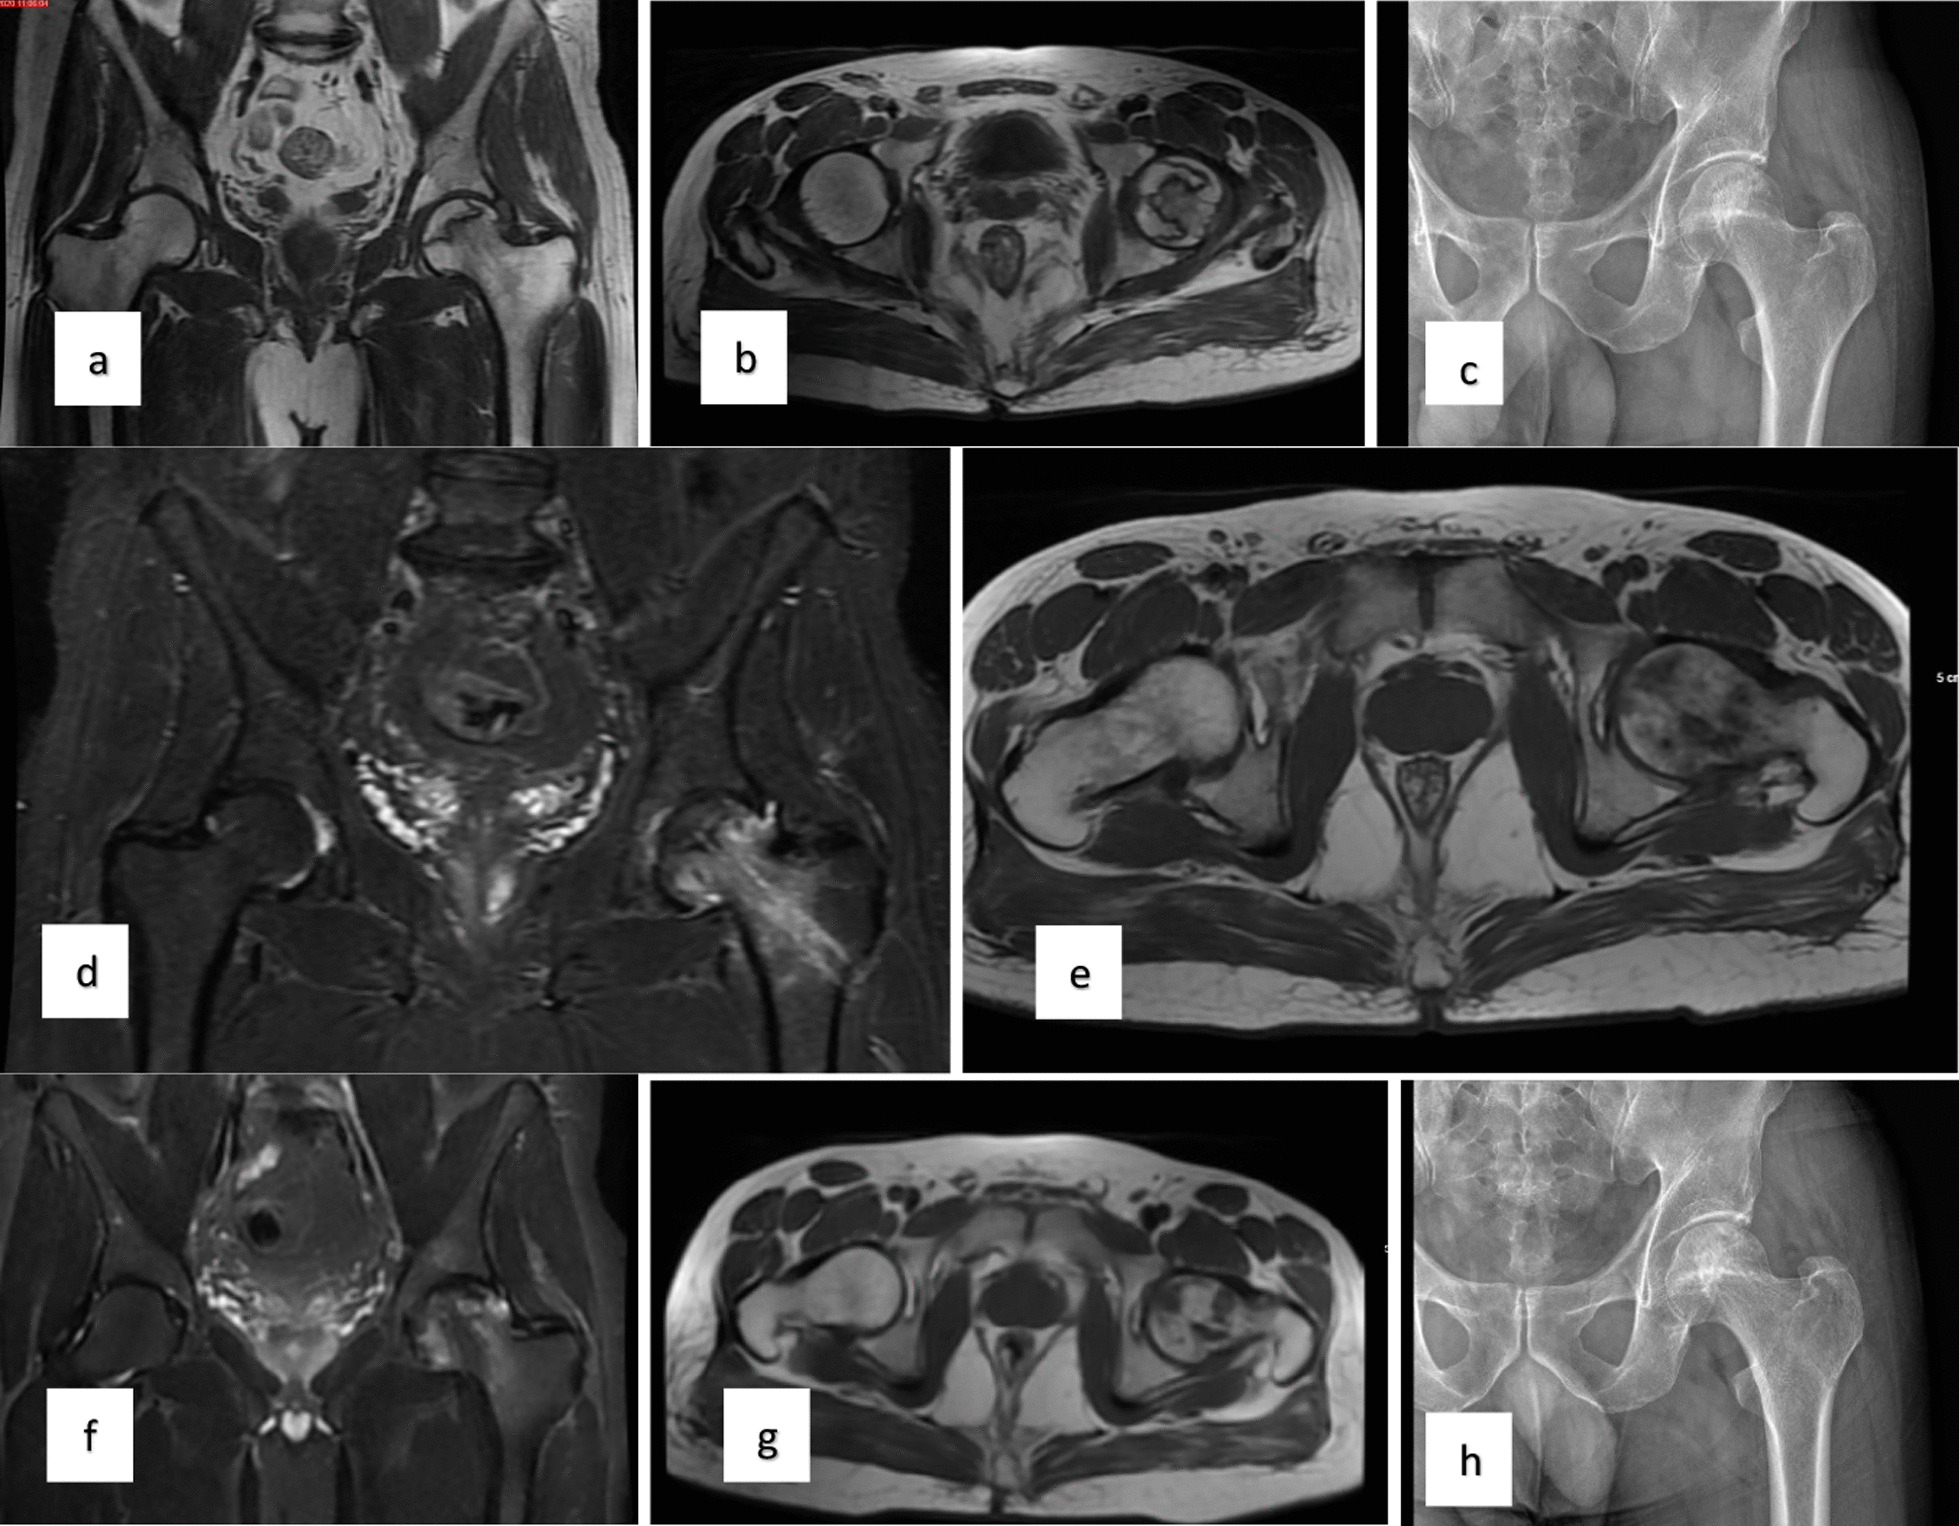

圖1:a–c左股骨頭缺血性壞死患者的術前MR和X射線圖像,d-e術后3個月的MR,f–h : 術后第二年的MR和X射線圖像

對患者的術前、3個月、6個月、1年和2年隨訪進行評估(圖1)。